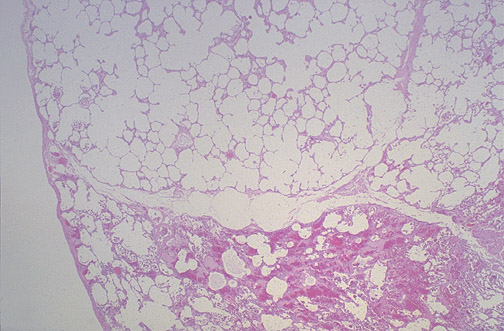

The dilated air spaces seen here are just beneath the pleura to the left. This is paraseptal, or distal acinar, emphysema. This condition is related to focal scar formation, not smoking.